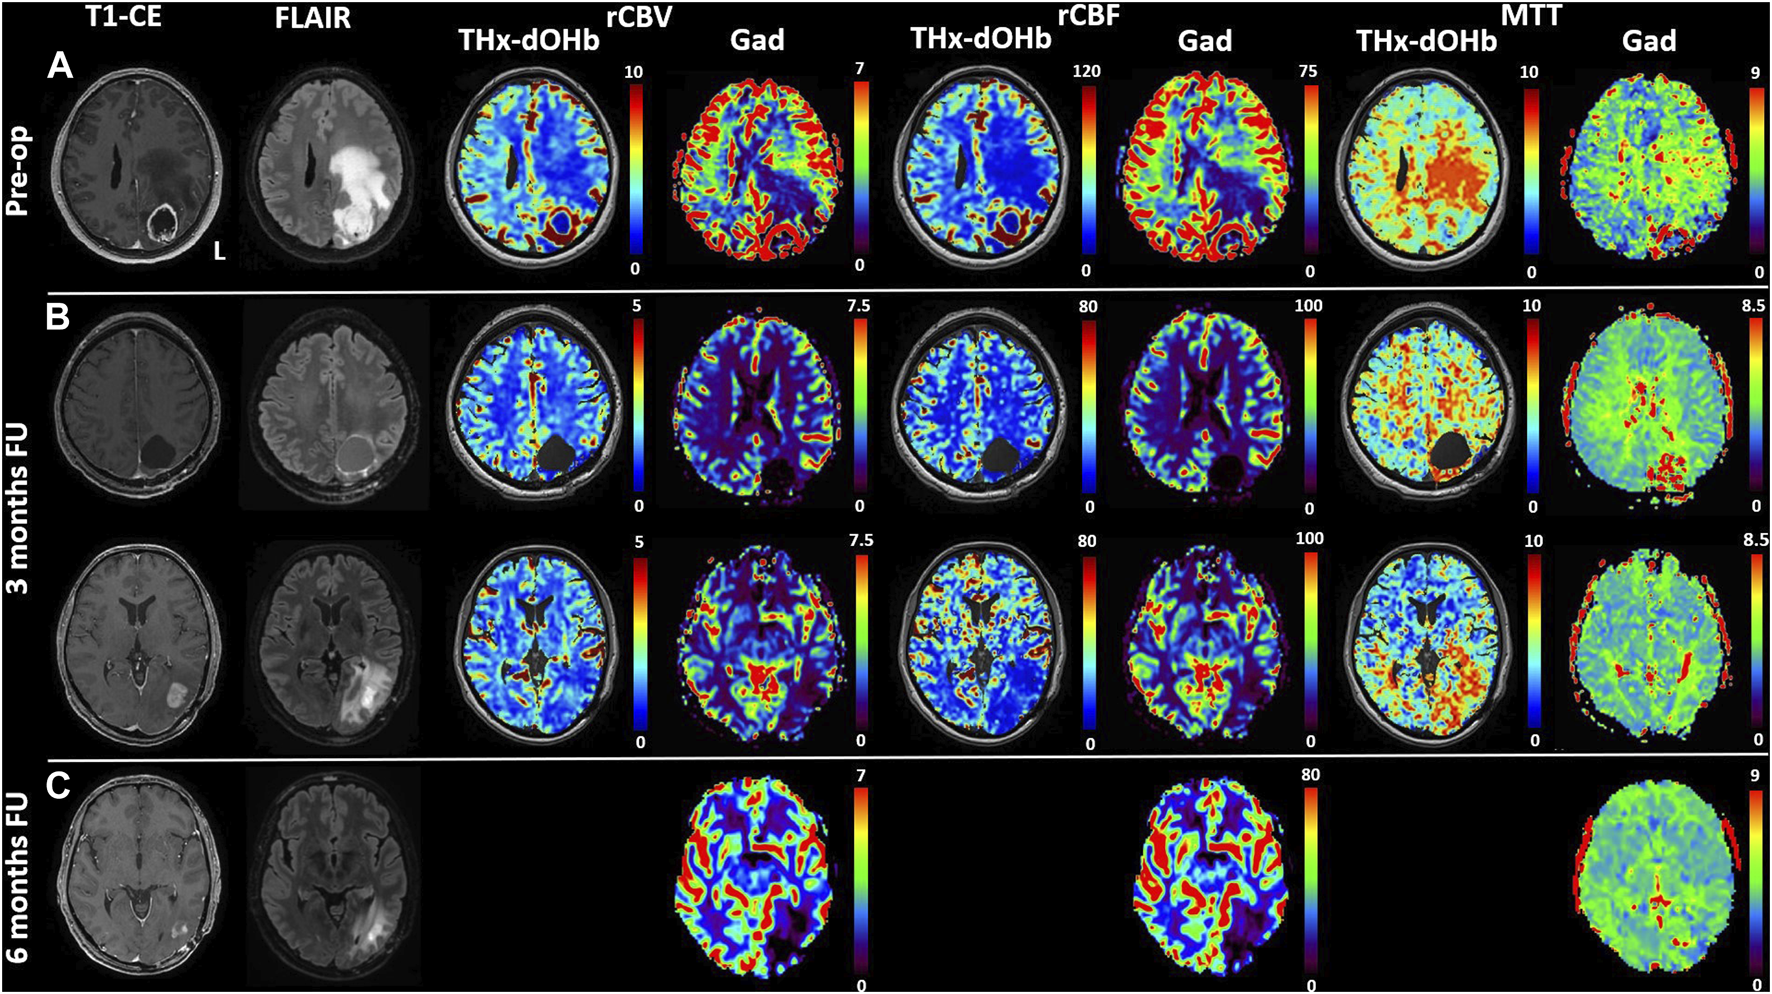

FIGURE 4

Comparison of transient hypoxia induced-dOHb perfusion maps with DSC-Gad MRI perfusion maps in three illustrative patients with diffuse cerebral glioma. T1-CE, T2-FLAIR, rCBV, rCBF and MTT obtained with transient hypoxia induced-dOHb and standard gadolinium MRI perfusion maps are displayed for three patients with cerebral diffuse glioma. (A). Patient 2, left frontobasal glioblastoma. (B). Patient 7, right middle temporal gyrus astrocytoma G2. (C). Patient 9, left temporopolar glioblastoma. Arrowheads pointing at relevant tumor areas to facilitate comparison between transient hypoxia induced-dOHb and gadolinium perfusion. Note: There is excellent congruence between Gd and d-OHb maps except for patient B, where tumor MTT values are much higher in the transient hypoxia induced-dOHb perfusion maps as compared to the gadolinium perfusion (asterisk). The reason for this is uncertain but the finding could point to higher sensitivity of the dOHb method to MTT abnormalities.

Based on the availability of 2 transient hypoxia induced-dOHb perfusion scans for patient 4, a multifocal glioblastoma with lesions in left cuneus and precuneus, follow-up imaging from pre-to post-operative is shown and compared with gadolinium DSC (Figure 6). Transient hypoxia induced-dOHb BOLD perfusion maps display good spatial agreement with gadolinium-based DSC perfusion also in the longitudinal follow-up of a glioblastoma patient.

FIGURE 6

Comparison of transient hypoxia induced-dOHb and DSC-Gad MRI perfusion maps in a glioblastoma patient before resection (A) and during follow-up at 3 (B) and 6 months (C). Baseline and follow-up comparison of transient hypoxia induced-dOHb and gadolinium DSC-MRI perfusion maps in patient with multifocal glioblastoma with lesions in left cuneus and precuneus. Pre-operative T1-CE, FLAIR and transient hypoxia induced-dOHb perfusion as well as corresponding gadolinium DSC-MRI maps (A) as well as 3 months (B) and 6 months follow-up MRI (C), only DSC-MRI available). The patient was referred to our center after receiving an MRI on prescription from the general practitioner following persistent parietal headaches episodes, vertigo, visual disturbances, memory loss and speech difficulties. The first MRI showed, as depicted in Figure 5, a contrast-enhancing lesion surrounding a central necrotic area in the left precuneus with extensive perilesional edema as well as a smaller contrast-enhancing lesion in the left cuneus. Consistently with known higher perfusion in glioblastomas, both DSC-MRI and transient hypoxia induced-dOHb showed higher rCBV and rCBF in tumor tissue. Gross total resection of the two lesions was performed. Histological analysis confirmed the diagnosis of glioblastoma. As a consequence, after surgery the patient received concomitant radiochemoterapy with temozolomide followed by maintenance chemotherapy as per standard of care (Stupp Protocol). MGMT promoter methylation analysis revealed an unmethylated promoter. At 3 months follow-up, both DSC and transient hypoxia induced-dOHb MRI were repeated. Figure 5 (upper panel) shows the resection cavity with normal perfusion at its margins. The same follow-up MRI showed however an area of contrast enhancement surrounded by FLAIR hyperintensity caudally to the resected tumor. This lesion did not display neither in DSC- nor transient hypoxia induced-dOHb MRI increased perfusion, with the two techniques showing perfusion maps with good qualitative agreement. (Figure 5, lower panel). Another MRI performed at 6 months showed a regression of contrast enhancement and edema. This clinical case shows how transient hypoxia induced-dOHb preliminarily achieved good agreement with gadolinium DSC perfusion also in the follow-up of a glioblastoma patient, warranting further longitudinal validation in the follow-up of treated glioma patients as well as in treated brain metastases.